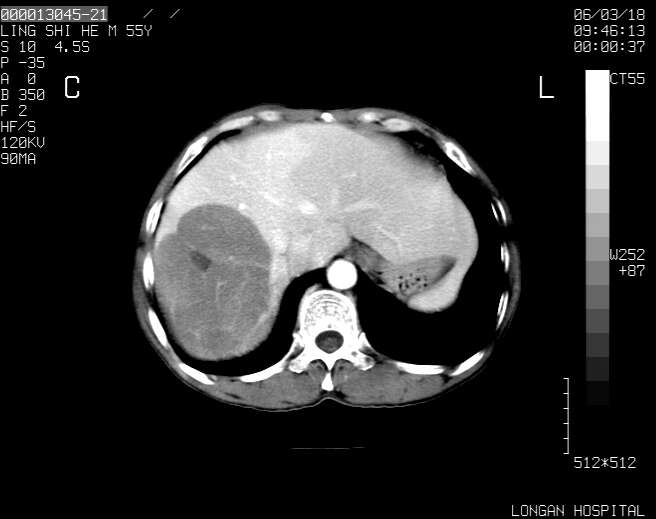

以下是引用guzhongliangddd在2006-3-21 22:13:00的发言:[br]病灶主要位于肝右叶的后份,内见异常血管,门脉主干及右支受侵{提示有癌栓形成},门腔间隙内见增大淋巴结。肝左叶内未见异常。

以下是引用zhuxinli在2006-3-22 1:23:00的发言:[br][br] 病灶主要位于肝右叶的后份,内见异常血管 .门脉右支截断,右叶前段早期强化(考虑动静脉漏),腹膜后肿大淋巴结,病灶逐渐强化,考虑为胆管细胞癌[br]